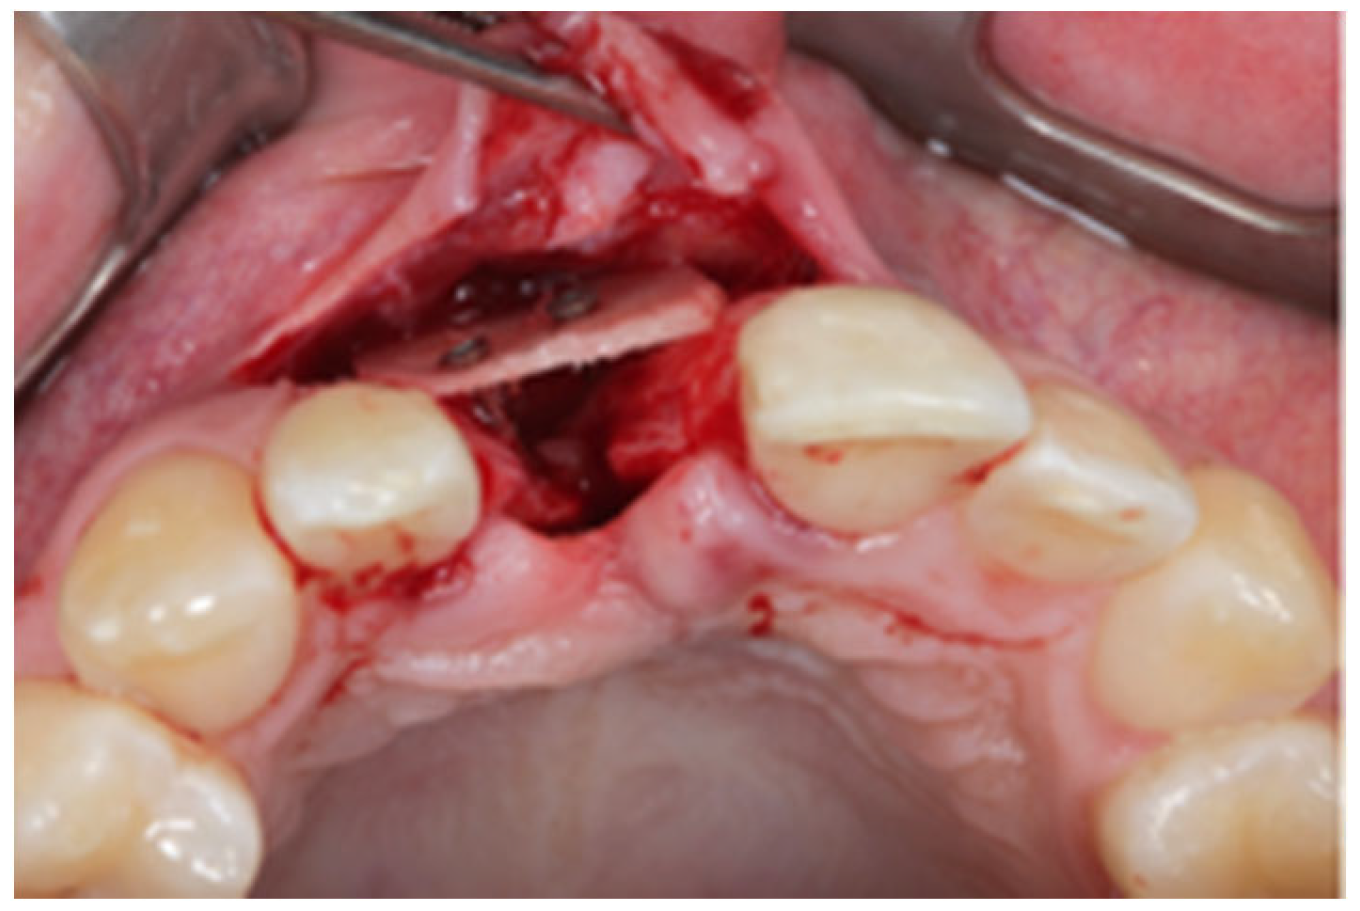

2.1. Surgical Technique